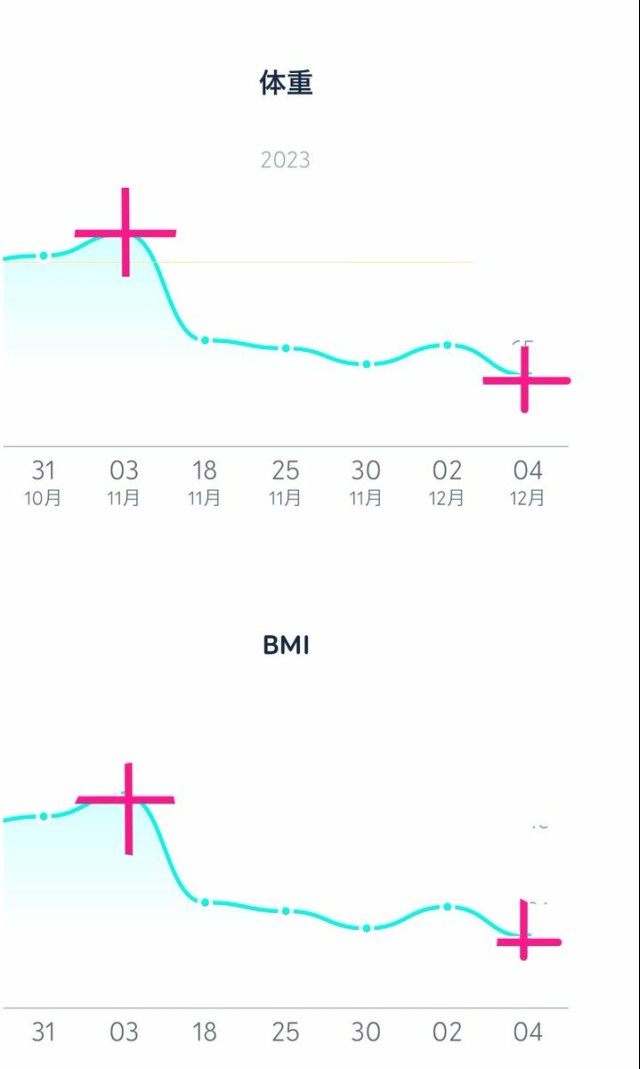

体重管理 ご飯もお菓子もしっかり食べてる方だと思うけど、妊娠前が大食いだったからか体重がなかなか増えない けど赤ちゃんは1000g超えてすくすく育ってるみたいだから病院で指摘されるまでは気にせず過ごします〜 昨日は夜ごはんのお米を炊くの忘れて、米なしにしたからガクッと落ちたのかも??